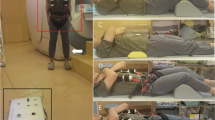

Axial loading of the spine

Axial loading of the spine was performed using a non magnetic compression device and a harness (DynaWell, DynaMed AB, Stockholm, Sweden) [17]. When loaded the patient was lying supine with extended hips and knees. To prevent flexion of the spine during compression, a small cushion was placed beneath the lumbar spine. The feet were positioned against a footplate on the compression device. The harness worn by the patient was attached to the compression device using side straps, which were tightened for axial loading of the lumbar spine. The load regulated by tightening or loosening adjustment knobs on the compression device, was registered on special indicators.

The external load was calculated to approximately 50% of the subject’s body weight, with equal load distribution on both legs. The load was applied for at least 5 min, after which axial T1- and T2-weighted sequences were performed.